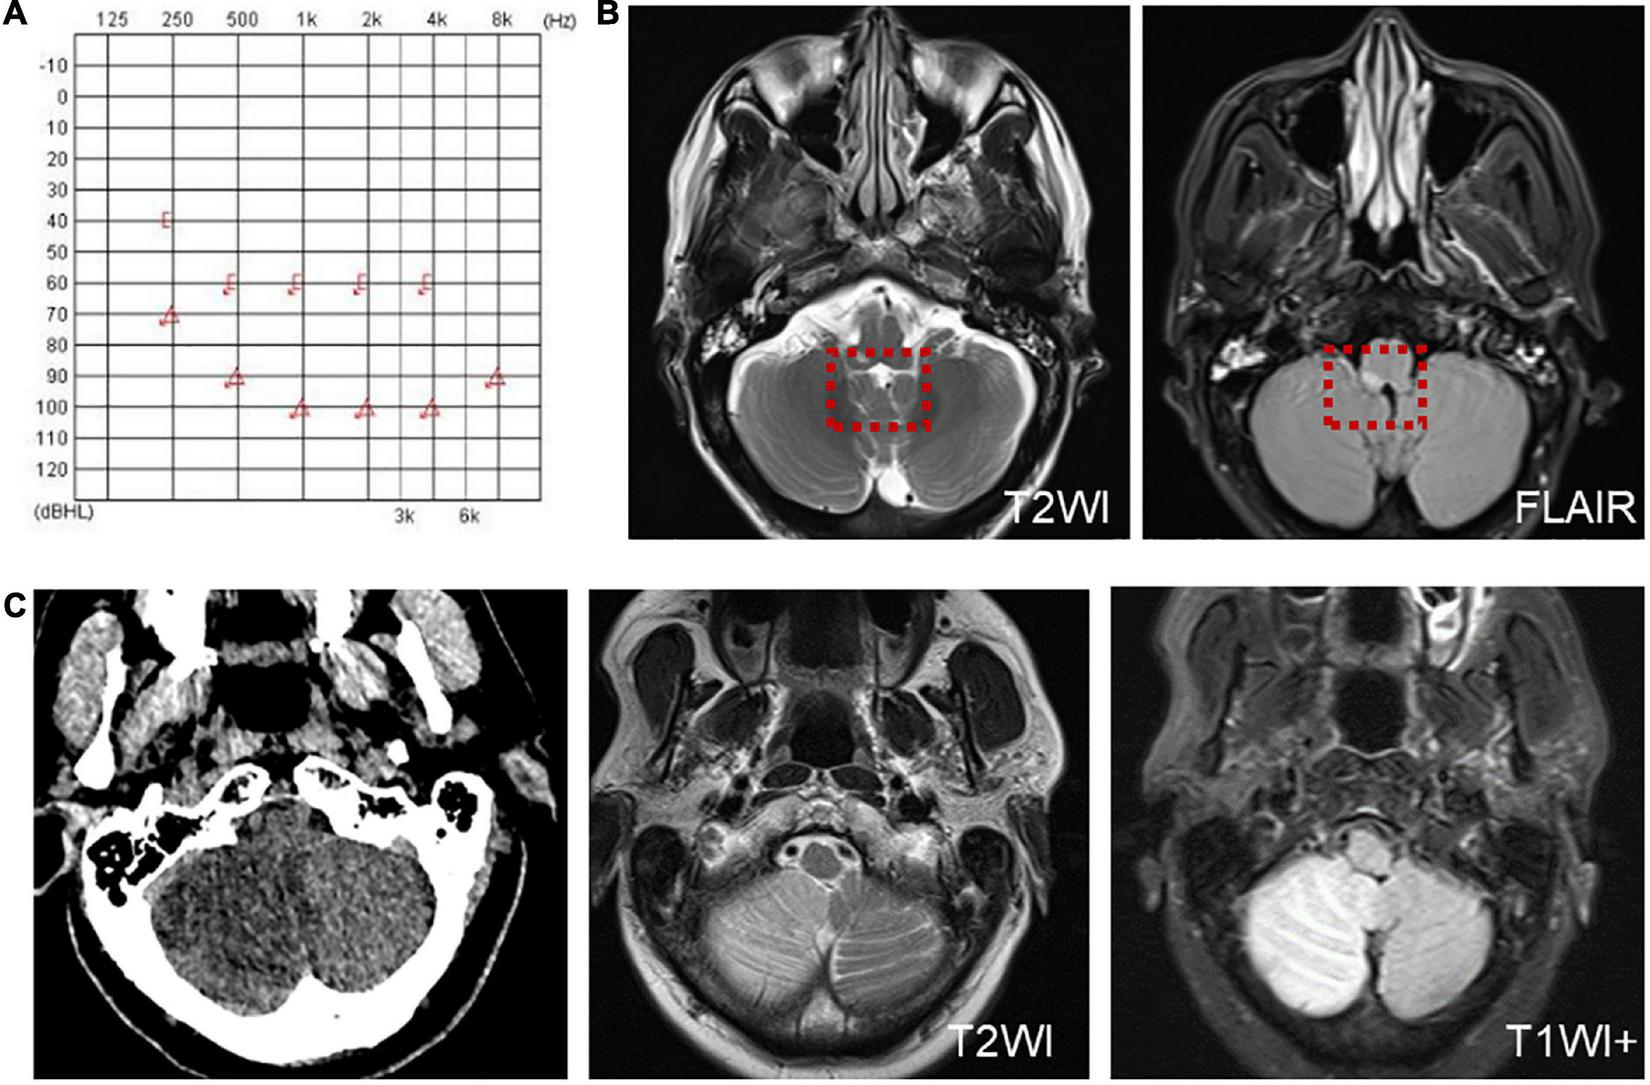

Another patient presented with continuous dizziness and sudden bilateral hearing loss; MRI revealed extensive infarction of the brainstem and cerebellum. PTA showed bilateral sensorineural hearing loss (Figure 5A), and brain MRI revealed lacunar foci in the bilateral basal ganglia (Figure 5B). The symptoms of both patients with cerebral infarction included vertigo with nausea and vomiting for 1 day, accompanied by DBN (Supplementary Video 3A). Brain MRI revealed bilateral basal ganglia and paraventricular infarcts. The other two patients had brainstem and basal ganglia ischemia and presented with DBN (Supplementary Video 3B).

Figure 5. The PTA and MRI of the patient with extensive infarction of the brainstem and cerebellum. (A) PTA shows a bilateral sensorineural hearing loss in a patient with extensive infarction of the brainstem and cerebellum. (B) Brain MRI shows lacunar foci in the bilateral basal ganglia.